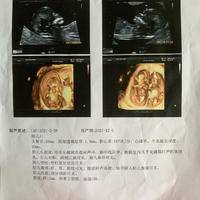

13周孕妇NT检查正常情况下的参考值一般是多少?

问题描述:我现在怀孕已经13周了,上次产检的时候医生说13周的时候可以做一个nt检查,好筛查一下胎儿有没有畸形或是心脏病之类的问题,所以这次我就打算加一个nt检查的项目,在去医院检查之前,我想先在网上问一下正常情况下这个检查的参考值一般是多少啊?最佳回答:13周孕妇的NT检查正常参考值一般在2.5mm以下。NT检查是胎儿颈项透明带的厚度,可以在孕期11周到13周+6天之间进行检测,是孕期非常重要的...